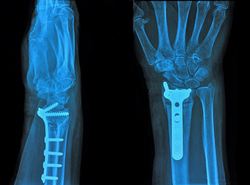

Mit der zunehmenden Zahl älterer Menschen und Unfallhäufigkeit steigt seit einigen Jahren auch die Nachfrage nach orthopädischen Implantaten. Implantate können die Knochenheilung beschleunigen und damit Kosten durch Arbeitsausfälle und Krankenhausaufenthalte senken. Eine neue Generation von Implantaten aus dreidimensionalen (3D) Gerüsten soll nun die Wachstum und Differenzierung von Stammzellen stimulieren. Hierfür muss allerdings die Mikroumgebung bzw. Nische des Implantatsubstrats sorgfältig konzipiert werden. Schwerpunkt des EU-finanzierten Projekts PLASMANANOSMART (Plasma- and electron beam-assisted nanofabrication of two-dimensional (2D) substrates and three-dimensional (3D) scaffolds with artificial cell-instructive niches for vascular and bone implants) war die Entwicklung funktioneller 2D-Substrate oder 3D-Gerüste für kardiovaskuläre und Knochenimplantate. Mit modernsten Nanofertigungsverfahren wurden künstliche Zell-instruktive Nischen erzeugt, in denen sich Stammzellen zu osteogenen oder vaskulären Zelllinien differenzieren. Die Forscher testen neue Materialien und optimierten deren Oberflächenstruktur durch Beschichtung mit Metalllegierungen und Hydroxylapatit (HA). Der HA-Film kann dann je nach Morphologie, Stöchiometrie und Dicke angepasst werden und die Zelladhäsion verbessern. Weiterhin wurde ein multifunktionales Biokomposit erzeugt, das mit HA und antibakteriellen Silber-Nanopartikeln beschichtet ist. Da Adhäsion, Proliferation und Differenzierung der Zellen wesentlich von den Oberflächeneigenschaften des Implantats abhängen, wurden verschiedene diesbezügliche Parameter von Polymergerüsten untersucht. Mit verschiedensten Methoden wurden Struktur, Porosität und Verteilung der Nanopartikel auf den Polymergerüsten wie auch biologische Abbaubarkeit und Korrosionsbeständigkeit untersucht. Dabei zeigten Röntgenanalysen, dass anorganische Partikel in den Polymerstoffen deren mechanische und biologische Eigenschaften verbessern können. Insgesamt ist das Marktpotenzial der Polymere von PLASMANANOSMART für orthopädische Implantate enorm. Der innovative Bioengineering-Ansatz gewährleistet eine dauerhafte Unterstützung des implantierten Gewebes, sodass Kosten durch Nachoperationen entfallen.